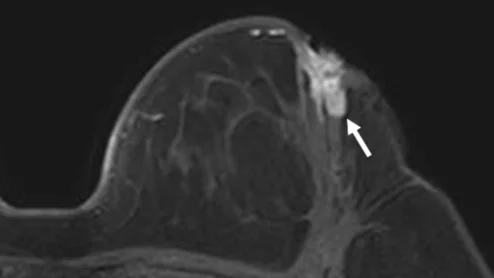

Thanks to AI, clinicians can use mammograms to do a lot more than identify signs of breast cancer. Researchers explored data from nearly 50,000 patients, presenting their findings in Heart.